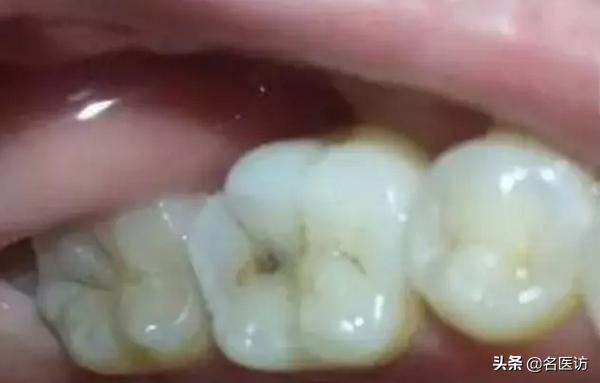

牙齿龋坏

牙齿龋坏是渐进性的破坏牙齿的过程。

牙齿龋坏的深度越靠近牙髓神经,牙齿的敏感症状越明显,所以一旦发现牙齿龋坏应尽快补牙。